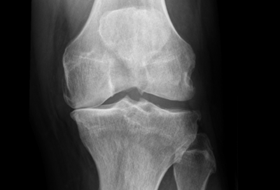

ViaSana wordt genoemd in een artikel over de toegevoegde van PROMs in Nederland. Wetenschapcoördinator Yvette Pronk legt uit dat de uitkomsten dankzij een zeer hoge respons van 80% voor verschillende doeleinden gebruikt kunnen worden. Bijvoorbeeld om medisch specialisten onderling te vergelijken. En om bij een nieuwe collega het handelen zo nodig bij te sturen. De benchmarkgegevens zijn ook te gebruiken om verbeterdoelstellingen te formuleren en de uitkomsten door de jaren heen te monitoren.

Een ander belangrijk doel is het terugkoppelen van de uitkomsten op groepsniveau naar de patiënt. Dit gebeurt onder andere gedaan via een app en de website van de kliniek. Wat kan een gemiddelde patiënt weer na de behandeling? En is de pijn volledig verdwenen? Deze informatie helpt de patiënt bij het kiezen van een behandeling. En geeft een goed beeld wat er van het behandelresultaat te verwachten is gedurende het revalidatietraject. Dat patiënten deze informatie waarderen, blijkt onder andere uit de PREMs die meten hoe patiënten de zorg en de informatie ervaren hebben.